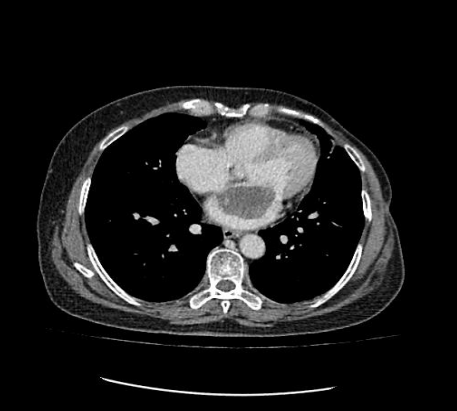

通訊員許欣報道:近日,我院心胸外科、麻醉科、手術(shù)室通力合作,為一名身患左房粘液瘤患者成功實施了胸腔鏡輔助下微創(chuàng)左房粘液瘤切除術(shù)。

患者為一57歲的女性,心慌、胸悶的癥狀已有年多,一直以為是“感冒”而沒放在心上。最近經(jīng)人介紹到我院檢查,經(jīng)心臟超聲檢查發(fā)現(xiàn)左心房上長了一個雞蛋大小的黏液瘤。雖說是良性的,但生長位置在二尖瓣口,如果黏液瘤碎片或瘤體表面血栓脫落,可發(fā)生體循環(huán)或肺循環(huán)的栓塞,隨時有猝死的危險。以往此類疾病必須通過傳統(tǒng)胸部正中切口實施手術(shù),病人術(shù)后要經(jīng)過3-6個月左右的恢復(fù)期,患者創(chuàng)傷大、恢復(fù)慢、出血較多、切口瘢痕明顯、心理負(fù)擔(dān)重,無論是對身體還是心理都是一次嚴(yán)重創(chuàng)傷。為患者實施全胸腔鏡技術(shù)摘除左心房黏液瘤手術(shù),在不破壞患者破壞胸骨穩(wěn)定性的前提下,只需在患者胸壁上開2個“鑰匙孔”樣大小觀察孔和1個4cm的操作孔即可進(jìn)行手術(shù),最大限度減少術(shù)后疼痛和創(chuàng)傷,縮短術(shù)后恢復(fù)時間。

據(jù)悉,胸腔鏡微創(chuàng)心臟手術(shù)是目前世界上頂級的微創(chuàng)心臟手術(shù),對外科醫(yī)生的經(jīng)驗和技術(shù)要求高。適合的病種包括二尖瓣病變、三尖瓣病變、房間隔缺損、室間隔缺損、左心房或右心房腫瘤等,尤其對左心瓣膜術(shù)后發(fā)生的三尖瓣重度關(guān)閉不全需要再次手術(shù)的患者具有極為突出的優(yōu)勢。